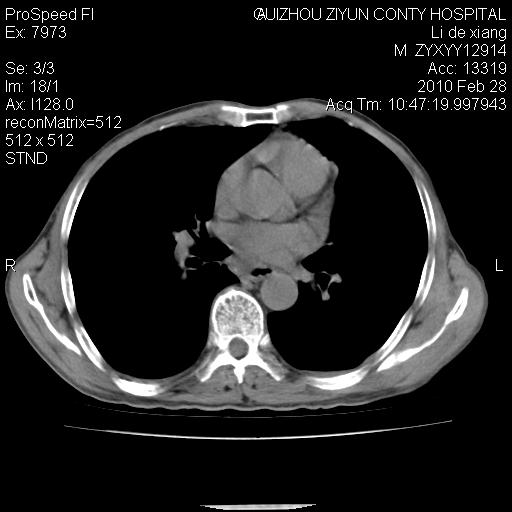

标题: CT24776:男 71Y 咳嗽咳痰胸痛两月,伴声音嘶哑。 [打印本页]

标题: CT24776:男 71Y 咳嗽咳痰胸痛两月,伴声音嘶哑。

左侧中央型肺癌伴左肺上叶阻塞性肺炎及节段性不张可能性大,建议纤支镜检查!

左侧中央型肺癌伴左肺上叶阻塞性肺炎及节段性不张可能性大,建议纤支镜检查!纵隔淋巴结转移.

左肺门部肿块,伴左上肺斑块影,周边模糊,支持左肺中央型肺癌伴节段性不张及阻塞性肺炎,结合支气管镜检查。

患者有声音嘶哑,若时间长了,没改变,喉镜检查无异常,可考虑左侧喉返神经受累,因为:左侧喉返神经绕主动脉弓或肺动脉韧带的主动脉端,沿气管与食管之间的沟上行至颈部.

左上叶支气管狭窄,阻塞性病变,肺门肿块,纵隔及肺门淋巴结增大,中央性肺癌